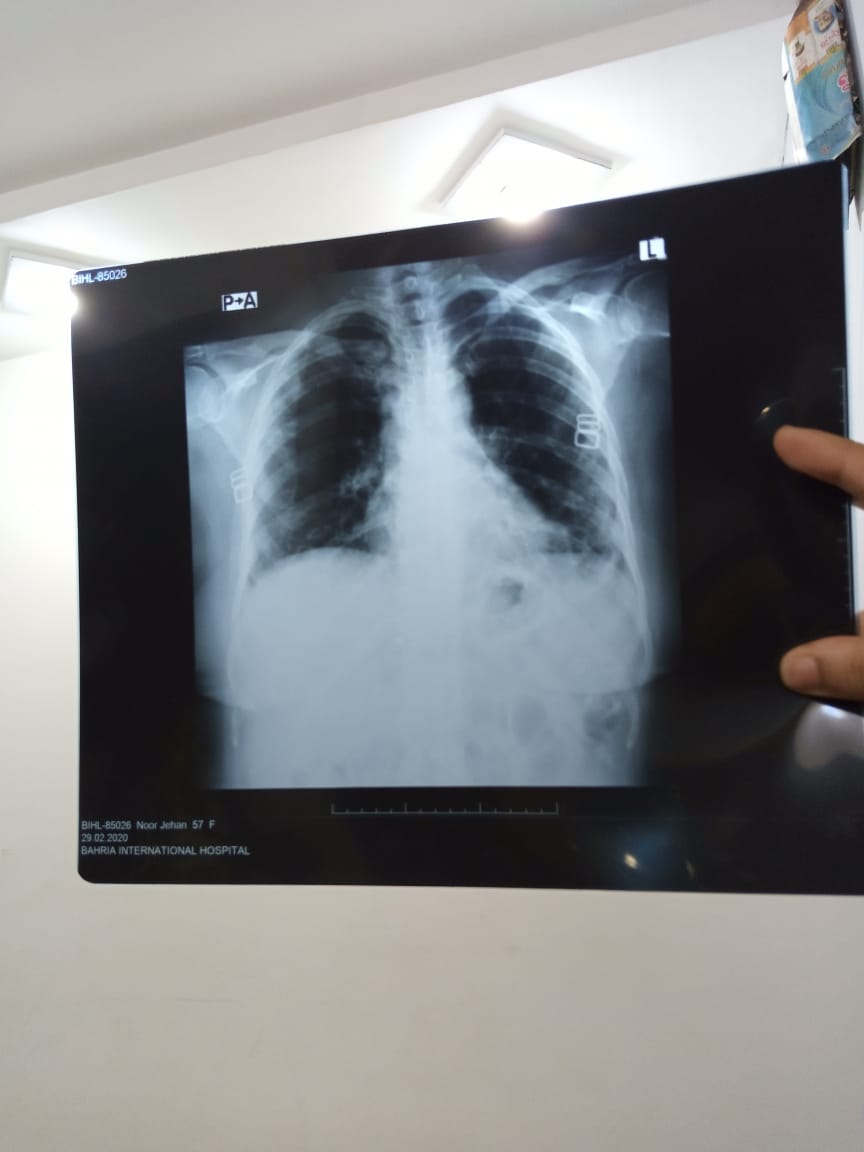

My mother has cough for quite some time these are her xray reports. Can any doc reccomend whats the issue who should we consult as in best pulmonologist in lahore

seems infection on left side.

cystic changes will be best commented on viewing x ray may need HRCT chest.

pt needs to be evaluated for diabetes.

For cough,treatment of infection and airflow limitation should be started.

Get Hrct chest dr irfan malik niazi hospital johar town

It is advised that your mother do HRCT scan and then see a pulmonologist for further management Taimour

Xray chest is one part of examination of the patient. You must consult any Pulmonologist. He must first examine the patient and then advise any investigation if needed. Prof Shamshad Rasul Awan